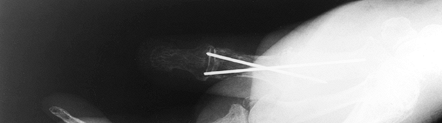

While ligament reconstruction and soft-tissue procedures are usually

preferred, in the arthritic thumb MCP joint, arthrodesis (Fig. 72.1, Fig. 72.2) provides a more lasting option and is generally preferred to arthroplastic techniques for a number of different disorders (36).

Figure 72.2. Metacarpophalangeal joint fusion, lateral view.